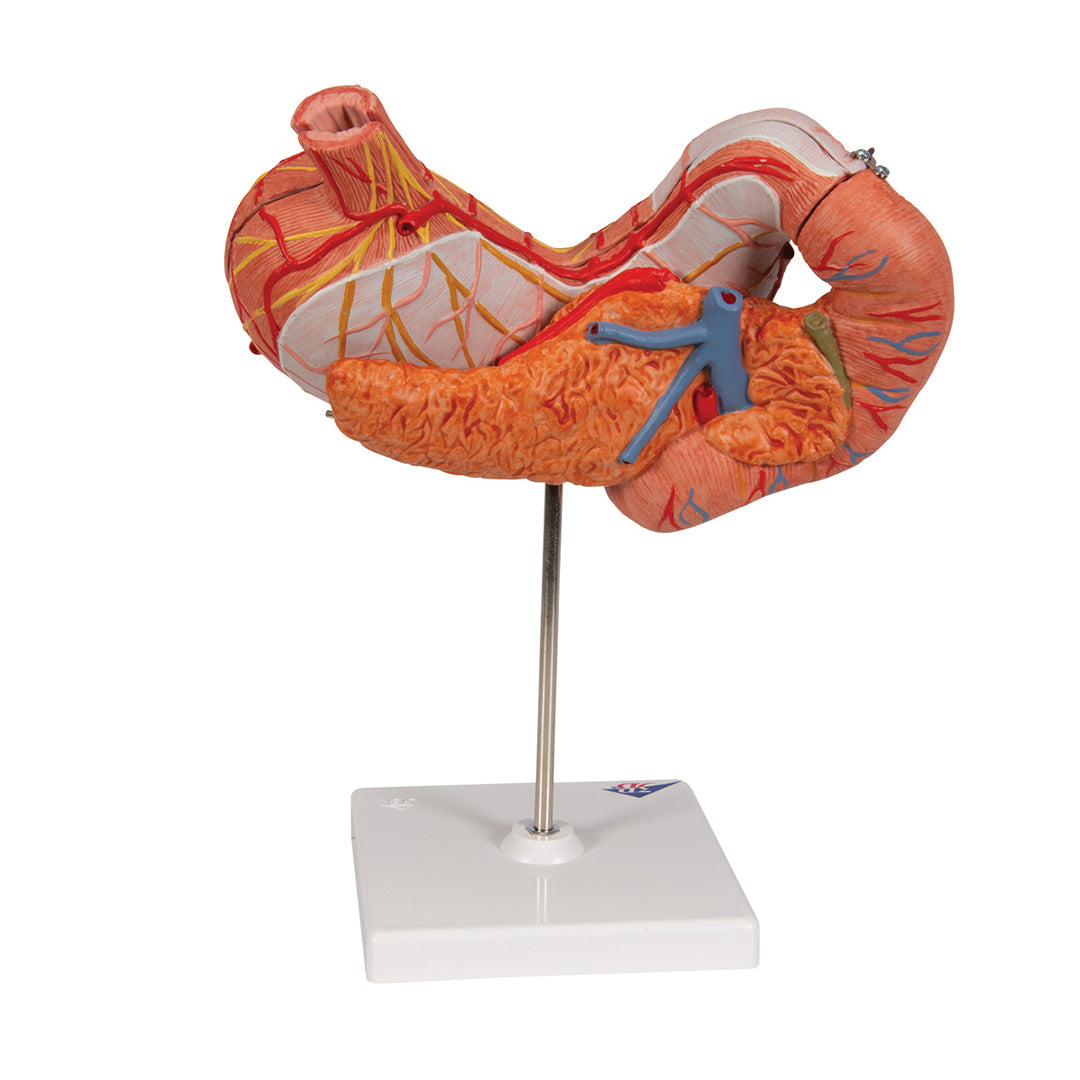

Estómago, en 3 piezas

Estómago, en 3 piezas

El modelo presenta las capas de la pared del estómago desde la cardia hasta el píloro.

La mitad delantera del estómago se puede retirar.

Se presentan:

• Parte inferior del esófago

• Conductos

• Nervios

• Duodeno

• Páncreas

Con soporte.

Peso 0.87 kg.

Dimension 25 x 22 x 12 cm